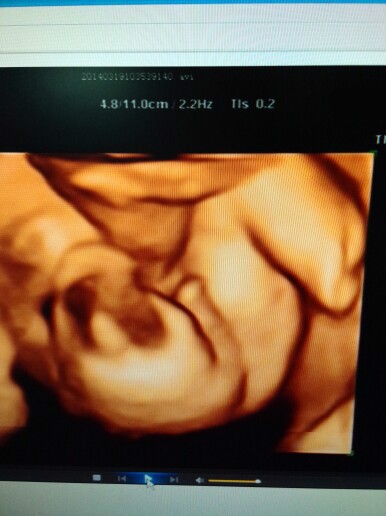

四维小弟弟照片竟如此清晰,男宝无疑,附症状!

四维高清小弟弟照:

这么清晰,是不是蛮震惊的,姐妹们来接棒吧!